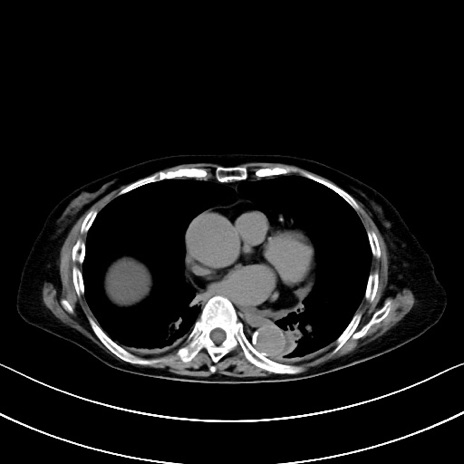

症例40(横断像)他院1日前

横断像

他院CT